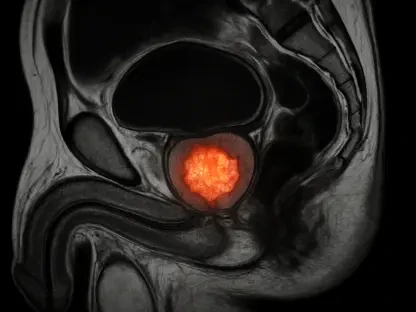

At the heart of Medtronic’s financial upswing lies its cardiovascular portfolio, which delivered an unprecedented $3.44 billion in revenue for Q2 FY26, marking a 10.8% increase from the prior year. This represents the strongest growth in this segment in over a decade, driven predominantly by the pulsed-field ablation (PFA) franchise. The PFA technology, designed to treat abnormal heart rhythms with enhanced safety and efficacy, reported a staggering 71% growth rate in the quarter, accelerating from nearly 50% in the previous one. Key products like the PulseSelect PFA system and the recently FDA-approved Sphere-9 Dual Energy Catheter with Affera Mapping System have been instrumental in this surge. Notably, the US market alone saw over 300% growth, complemented by significant gains internationally, highlighting the global appeal and clinical acceptance of these innovations.

The success of the cardiovascular segment extends beyond mere revenue figures; it reflects Medtronic’s strategic emphasis on addressing critical healthcare needs through cutting-edge solutions. The PFA franchise’s rapid adoption by clinicians stems from its ability to offer a safer alternative to traditional ablation methods, minimizing risks to patients while improving outcomes. This technological edge has not only bolstered Medtronic’s reputation as an innovator but also expanded its market share in a segment where demand continues to rise. The FDA approvals of key PFA products in recent years have further accelerated this momentum, providing regulatory validation that enhances trust among healthcare providers. As cardiovascular diseases remain a leading global health concern, Medtronic’s focus on this area positions it to meet escalating demand with solutions that are both effective and accessible across diverse markets.